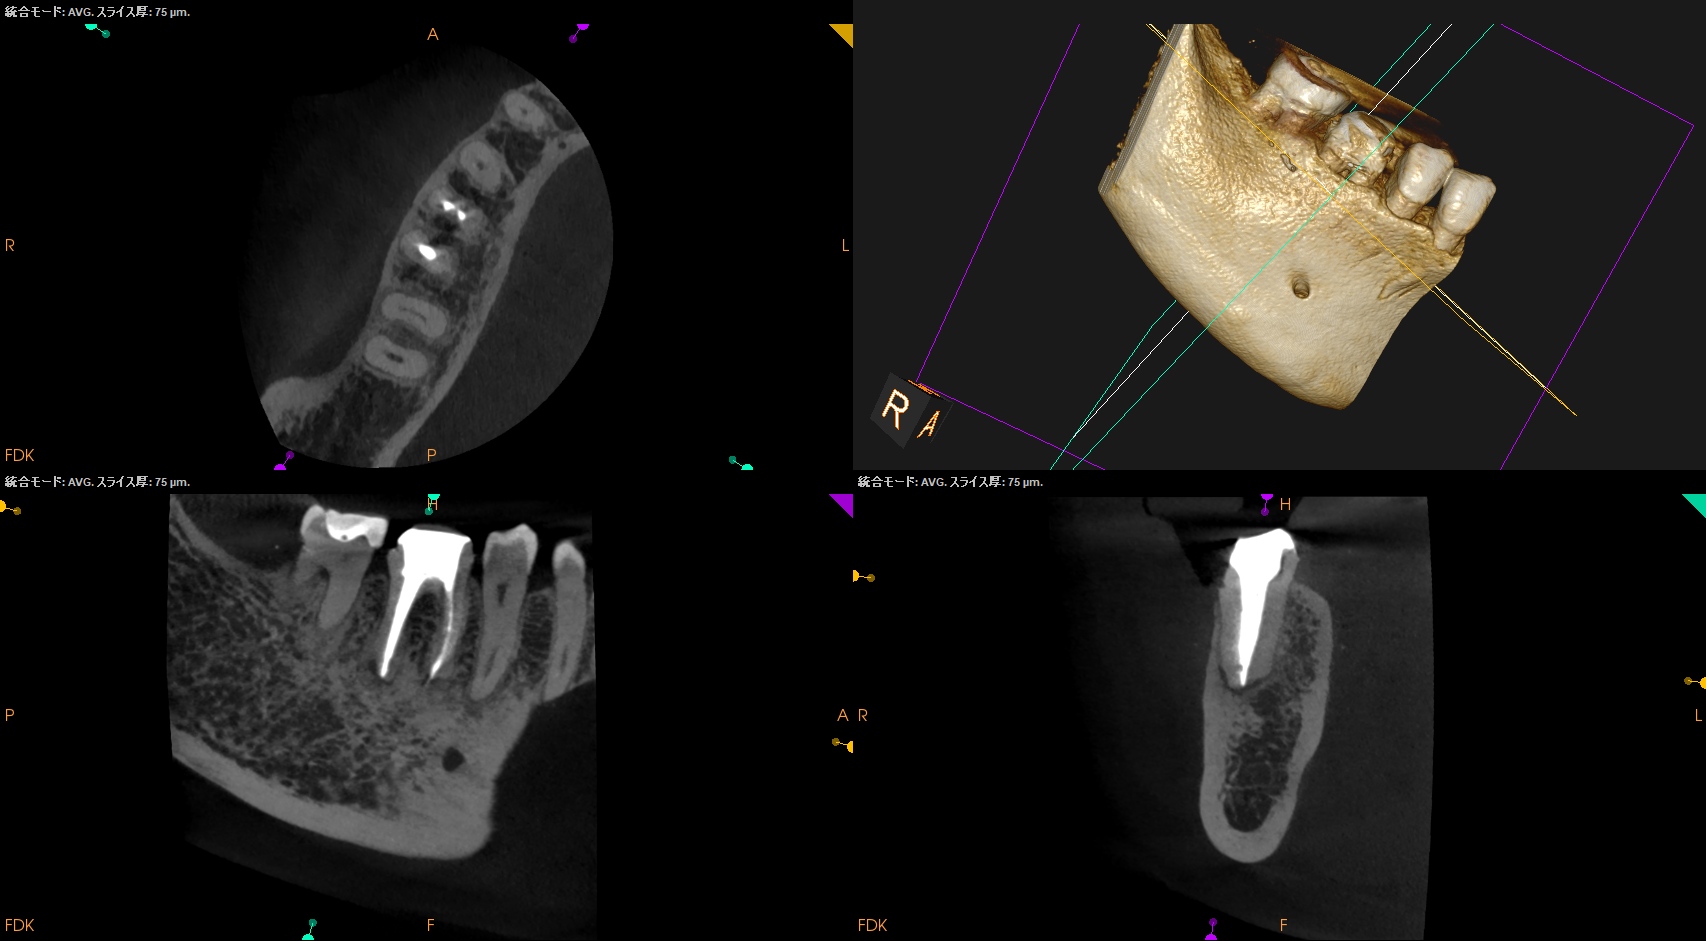

CBCT(2025.8.29)

#30

MB

ML

D

#31

MBとML,どちらがストレートか?と言えばMLの方だろう。

MLをメイン根管にしてMBはそこに合流するという風に形成・根充すべきだろう。